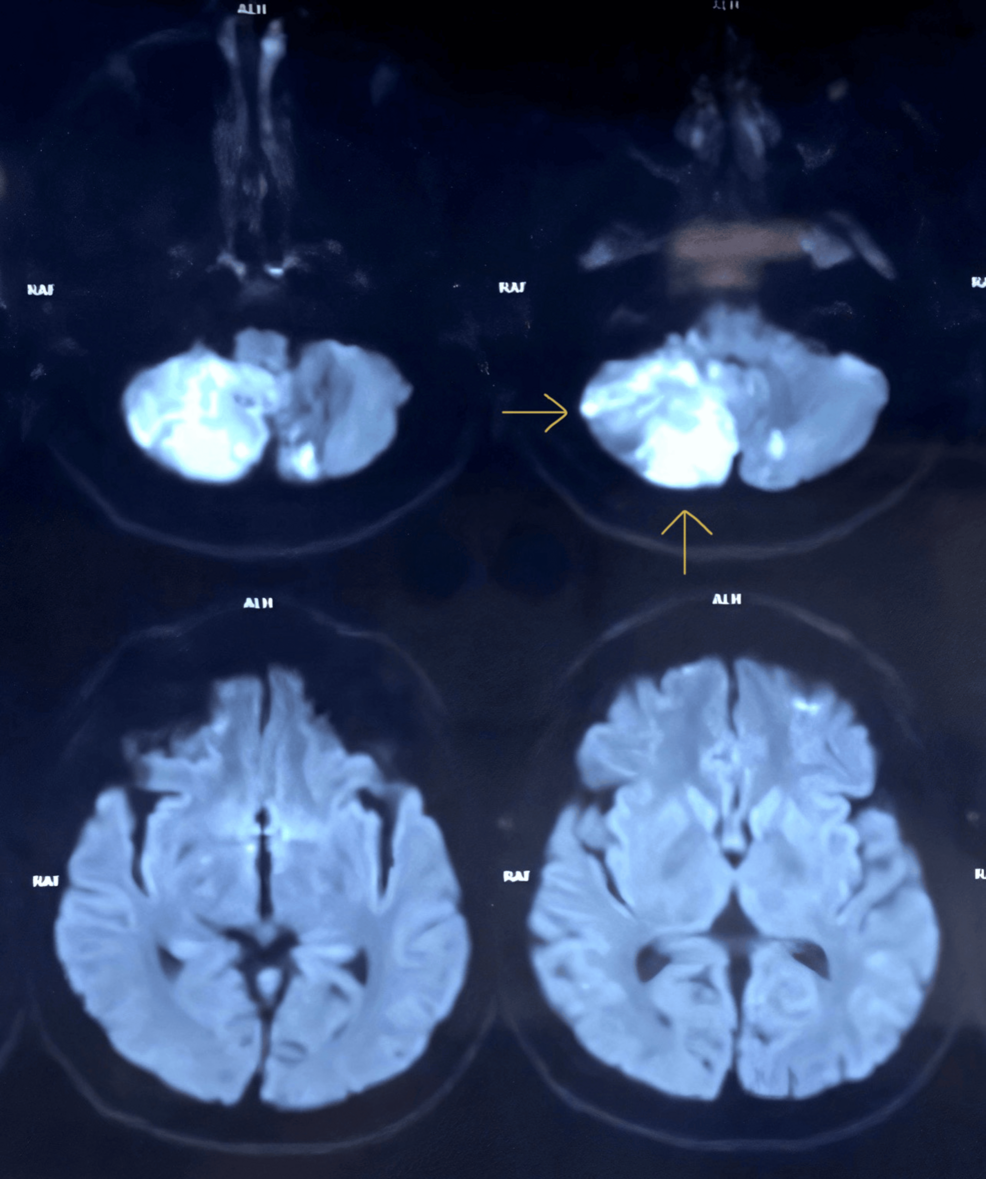

El estudio detalla la presentación clínica del paciente, las pruebas diagnósticas realizadas (incluyendo resonancia magnética cerebral) y el tratamiento administrado. Aunque los detalles específicos del tratamiento no se especifican en el resumen, la encefalitis herpética generalmente se trata con medicamentos antivirales como el aciclovir.